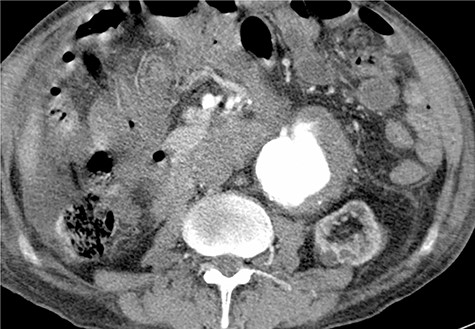

To minimize the risk of injury to renal allograft and avoid facing a hostile-abdomen, the patient was proposed to EVAR. Prior to intervention, upon contrast injection, the aneurysm and the corresponding clot containing the leakage were visualized (Video 1). A bifurcated endograft (Cook Zenith LP) was used and the main body was introduced through the left common femoral artery to reduce the duration of ischemia. The contralateral gate was cannulated and Lunderquist wire was advanced. The right-sided sheath was withdrawn up to the common femoral artery and the ipsilateral limb was deployed (Video 2). The post-operation course was uncomplicated with normal levels of serum creatinine. The patient was discharged 2 days later. One month later, a follow-up CT angiography was performed that demonstrated successful endovascular stent graft placement (Fig. 3).